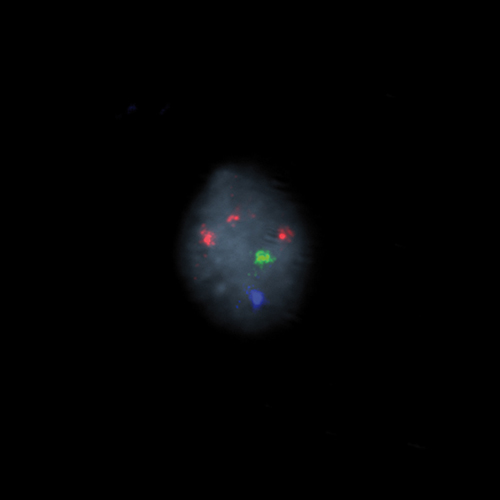

KBI-10503

1q21 / 8p21